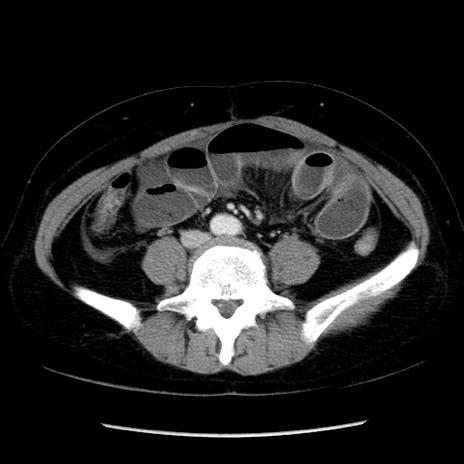

症例6(横断像)

【症例】50歳代女性

【主訴】下腹部痛

【現病歴】本日朝より下痢2回あり。 昼食を食べた後、嘔吐3回、下腹部痛認め、症状軽快せず、当院救急搬送。

最終食事:本日昼(生ものなし)。 昨日の夜、刺身を食ぺたとのこと。周囲に同様の症状の者なし。普段、排便は毎日あるとのこと。

【既往歴】卵巣癌術後(8年前に当院で卵巣摘出)

【身体所見】 意識清明、腹部:平坦、腸蠕動音→、やや硬、下腹部自発痛・圧痛あり、反跳痛あり、筋性防御なし。

【データ】WBC 16000、CRP 0.01